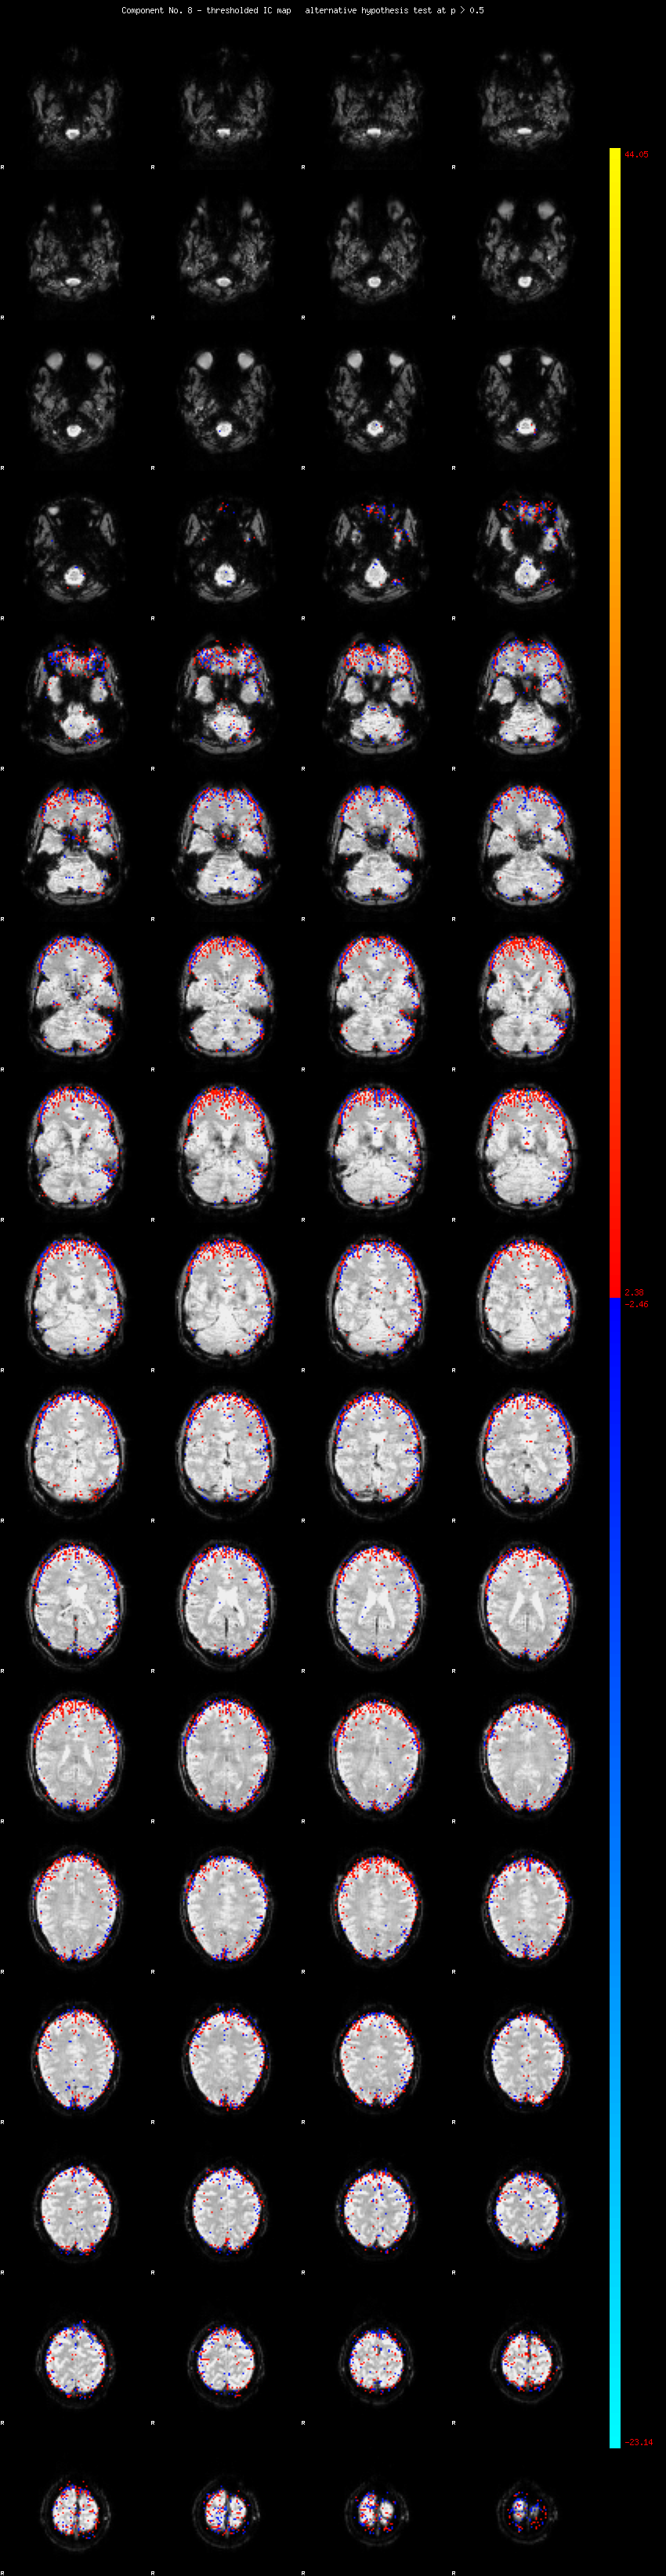

MELODIC Component 8

2.19 % of explained variance;     1.45 % of total variance

MMfit